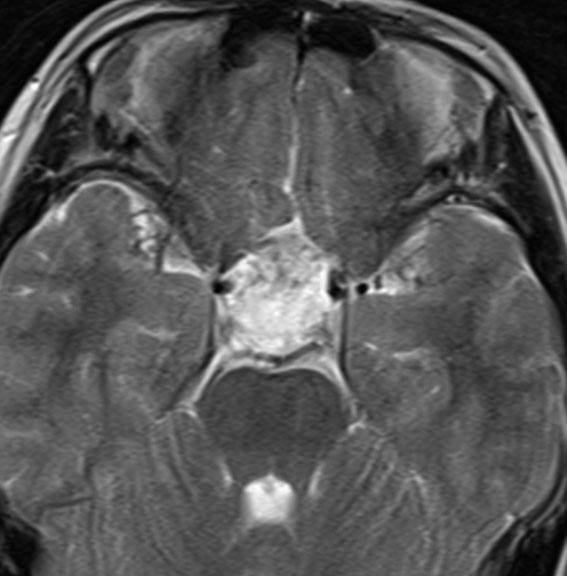

前床突起硬膜あたりから発生したもの

16歳で無症状で発見されました。左前床突起の硬膜に強く癒着していたものです。開頭手術で全摘出したのですが,左シルピウス列には油性のdebrisが散在していてすでにruptureがありました。内頸動脈,前大脳動脈,中大脳動脈には高度に癒着があり,ハサミで動脈壁から切り離すという危険な摘出でした。類皮のう胞は動脈や脳と高度に癒着を生じる腫瘍だと,術前に覚悟しなければなりません。取り残しての再手術ではさらに癒着と肉芽組織との戦いになります。

この部位は取り残して再発すると,内頚動脈や前大脳動脈を切断する羽目にもなるので,何としても1回目で全摘出します